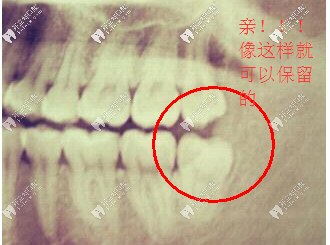

有的朋友對(duì)于拔智齒非??咕?,今天黃醫(yī)生就告訴大家哪些智齒是不用拔的!

1、智齒萌出,形狀正常,與前面的牙齒鄰接聯(lián)系正常,與相對(duì)的牙齒咬合正常。那么這顆智齒就能夠象其他牙齒相同表現(xiàn)它的咀嚼功用,就不需求拔除。

比較正的智齒不用拔除